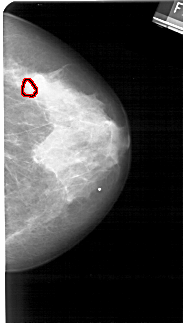

FILE: A_1270_1.RIGHT_CC.OVERLAY

TOTAL_ABNORMALITIES 1

ABNORMALITY 1

LESION_TYPE CALCIFICATION TYPE PLEOMORPHIC DISTRIBUTION CLUSTERED

ASSESSMENT 4

SUBTLETY 4

PATHOLOGY BENIGN

TOTAL_OUTLINES 1

BOUNDARY